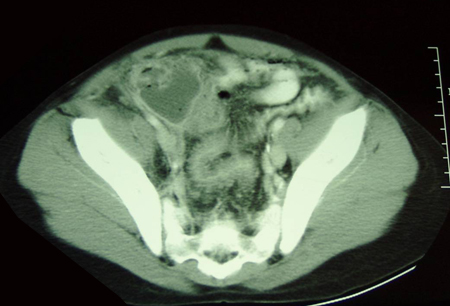

- CT scan abdomen and pelvis:

target lesion: intraluminal soft-tissue density mass with an eccentrically placed fatty area; reniform mass: high attenuation peripherally and lower attenuation centrally; sausage-shaped mass: alternating areas of low and high attenuation representing closely spaced bowel wall, mesenteric fat and/or intestinal fluid and gas

More - CT scan abdomen:

thickened inflamed bowel mucosa, thumbprinting, intestinal dilation or evidence of stricture; inflamed mesentery; intra-abdominal abscesses

More - CT scan abdomen and pelvis:

skip lesions, bowel wall thickening, surrounding inflammation, abscess, fistulas